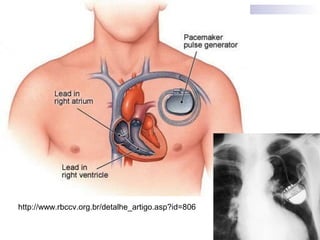

Marcapassos Cardíacos

Definição

São sistemas que monitoram constantemente o ritmo

menor que a programada.

Componentes

Marcapasso Endocavitário Definitivo

BICAMERAL